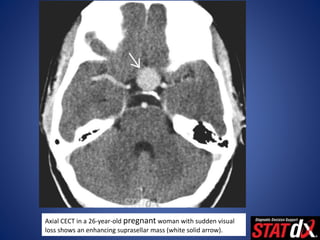

Axial CECT in a 26-year-old pregnant woman with sudden visual

loss shows an enhancing suprasellar mass (white solid arrow).

Axial CECT ina 26-year-old pregnant woman with sudden visual loss shows an enhancing suprasellar mass (white solid arrow).